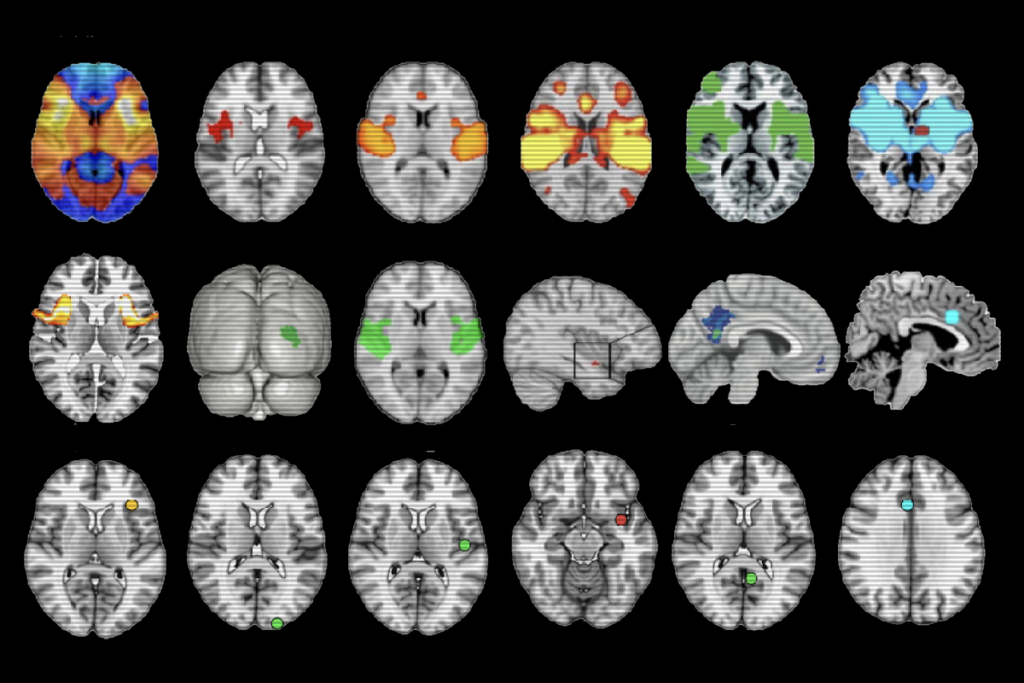

‘Overdue’ debate unfurls over neuroimaging method

After a January paper questioned the validity of an approach called lesion network mapping, its users are pressure testing their results.

‘Overdue’ debate unfurls over neuroimaging method

After a January paper questioned the validity of an approach called lesion network mapping, its users are pressure testing their results.

Methodological flaw may upend network mapping tool

The lesion network mapping method, used to identify disease-specific brain networks for clinical stimulation, produces a nearly identical network map for any given condition, according to a new study.

Methodological flaw may upend network mapping tool

The lesion network mapping method, used to identify disease-specific brain networks for clinical stimulation, produces a nearly identical network map for any given condition, according to a new study.